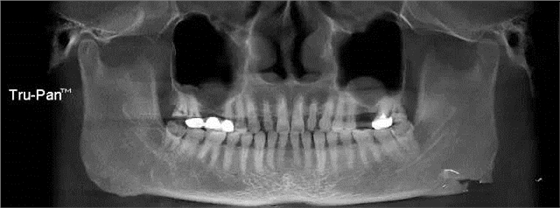

第九圖:上頜竇炎癥,提升前需要耳鼻喉科治療。